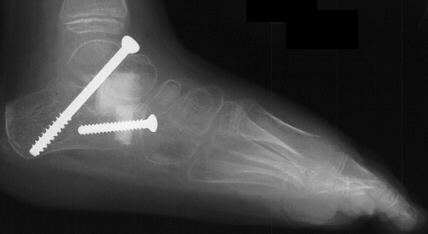

Postoperative X-rays:

- Left Talocalcaneal angle is 24 degrees, Talonavicular angle is 2 degrees

- Right Talocalcaneal angle is 28 degrees, Talonavicular angle is 2 degrees

The patient failed conservative management with bracing and therefore

had a bilateral subtalar arthrodesis with lateral column lengthening and

gastrocnemius lengthening

.

Post-operatively, the patient was placed in bilateral short leg casts and

allowed full weight bearing.

At 15 month follow-up the patient had a decrease in her popliteal angles

to 20 degrees and was ambulating with plantigrade feet in neutral varus/valgus

angulation.